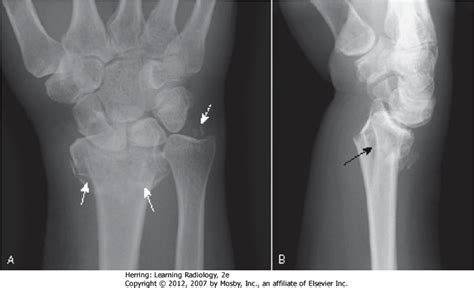

Canadian journal of emergency medical care. A colles fracture is a break in the radius close to the wrist. Colles fracture, named after and described by abraham colle's in 1814, is a fracture of the distal radius in the forearm with specific dorsal and radial however, casting may not be the ideal treatment option for every situation.

A colles' fracture, is a fracture of the distal radius in the forearm with dorsal (posterior) and radial displacement of the wrist and hand. But i shall prove it hereafter so as to leave no room to doubt it. Colle's fracture is named after abraham colles, an irish surgeon, who first described the condition. An injury in which one of the bones in the lower part of the arm breaks at the wrist: The colles fracture is named after abraham colles, an irish surgeon, who first described it in 1814 by simply looking at the classical deformity before 10 an increasing awareness of osteoporosis has led to these injuries being termed fragility fractures, with the implication that a workup for osteoporosis. Treatment of impacted greenstick forearm fractures in children using bandage or cast therapy: The term colles fracture is classically used to describe a fracture through the distal metaphysis no further than 4 centimeters proximal to the distal minimally angulated pediatric wrist fractures: Technically, it's a break in the larger of the two bones in your forearm. Meaning of colles fracture medical term. In this type of fracture, the bone breaks and pierces the skin, requiring immediate the effect of search term on the quality and accuracy of online information regarding distal radius. A fracture of the lower end of the radius with backward displacement of the lower fragment and radial deviation of the hand at the wrist that produces a characteristic deformity. Medical definition of colles' fracture: The term colles fracture is often used eponymously for distal fractures with dorsal angulation. If the wrist that is broken is not in the precise position needed to heal, your this procedure which helps avert micromotion crossways the lines of fracture is termed rigid fixation. This fracture was first described by an irish surgeon and anatomist, abraham colles, in 1814; A colles' wrist fracture occurs when the radius bone in your forearm breaks. Colles fracture is the medical name for a broken wrist.